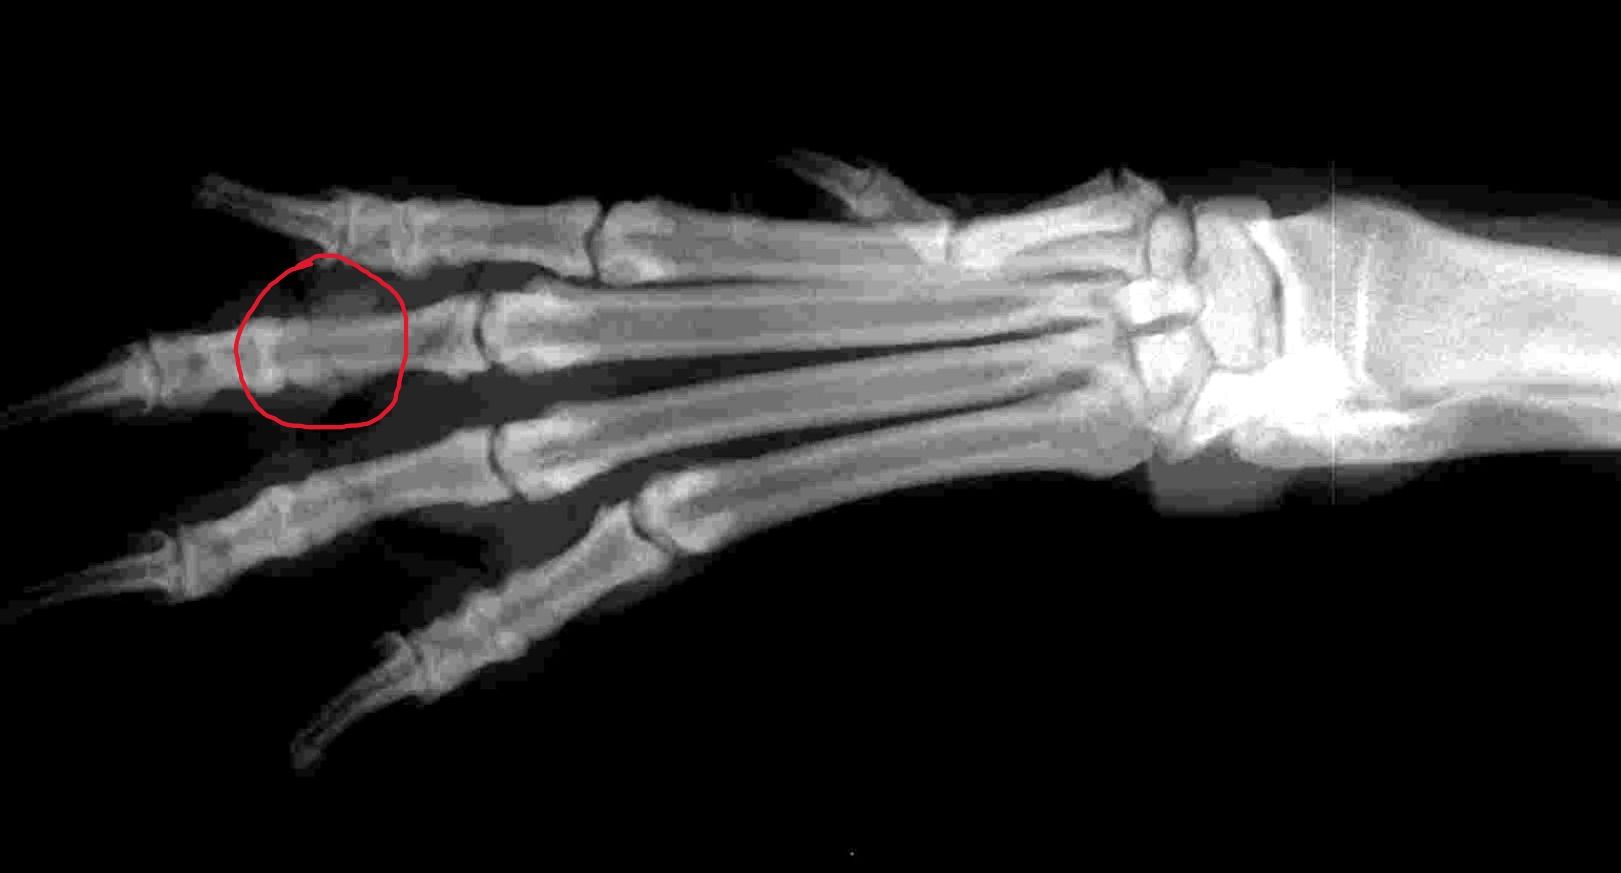

Bonjour, il y a 18 mois après avoir marché sur la patte de mon chien il s'est mis à être boiteux après chaque repos mais cela disparaissait en quelque pas, ne montrant pas d'autre douleur et ne voyant que ca s'améliore pas nous avons décidé de contacter ostéopathe qui avait tout remis en ordre pendant 4 mois mais elle continuait ses promenade habituelle et n'ayant jamais eu de repos car je pensais à quelque chose de moins grave que ca. Apres ses 4 mois une légère boiterie est revenu et re-osteo quelque temps après qui remets tout " en etat " pendant 2 mois, sachant que je ne savais pas encore pour la fracture avant le mois dernier donc elle creusait comme elle le souhaitait etc. Decembre encore une rechute de boiterie donc osteo et pensant à une entorse elle a été mise au repos pour la première fois de sa vie et voyant que ca ne passe pas vraiment on a refait une séance un mois après avec reprise d'activité mais toujours cette raideur mais plus de boiterie. C'est donc 1mois après cette séance que je l'avais laissé re creusé un peu et après repos une grosse boiterie était revenu, donc cette fois vétérinaire qui constate une gène a l'appuie sous une phalange et radio pour confirmer. Il a diagnostiqué une ancienne fracture qui a consolidé tout seul mais " mal cicatrisé " il m'a conseillé simplement de lui faire perdre du poids ( 4kg de trop ) et de prendre des compléments. 1 mois est passé j'ai repris les promenades en liberté en faisant attention ( plus de creusage ) elle a toujours une raideur après repos post balade mais je pense du peut être a son manque d'activité les mois dernier ? Sachant aussi qu'il n'y a pas d'arthrose à l'épaule ou au carpe et que l'osteopathe n'en avait pas senti non plus. J'ai reprogrammé une seance d'osteopathe dans 3 semaines pour lever ses compensations. Avez vous deja eu des expériences similaire ou des recommandation pour un cas comme cela ? Je vous joint la radio ci dessous. ( c'est la patte avant gauche )